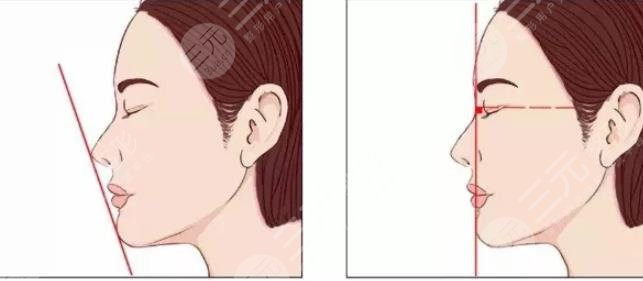

Q1:颏成型手术的原理是什么?

Answer:通过个性化的设计、修整、调整之后加以固定,从而改变下巴的形态,解决后缩以及前移的问题。